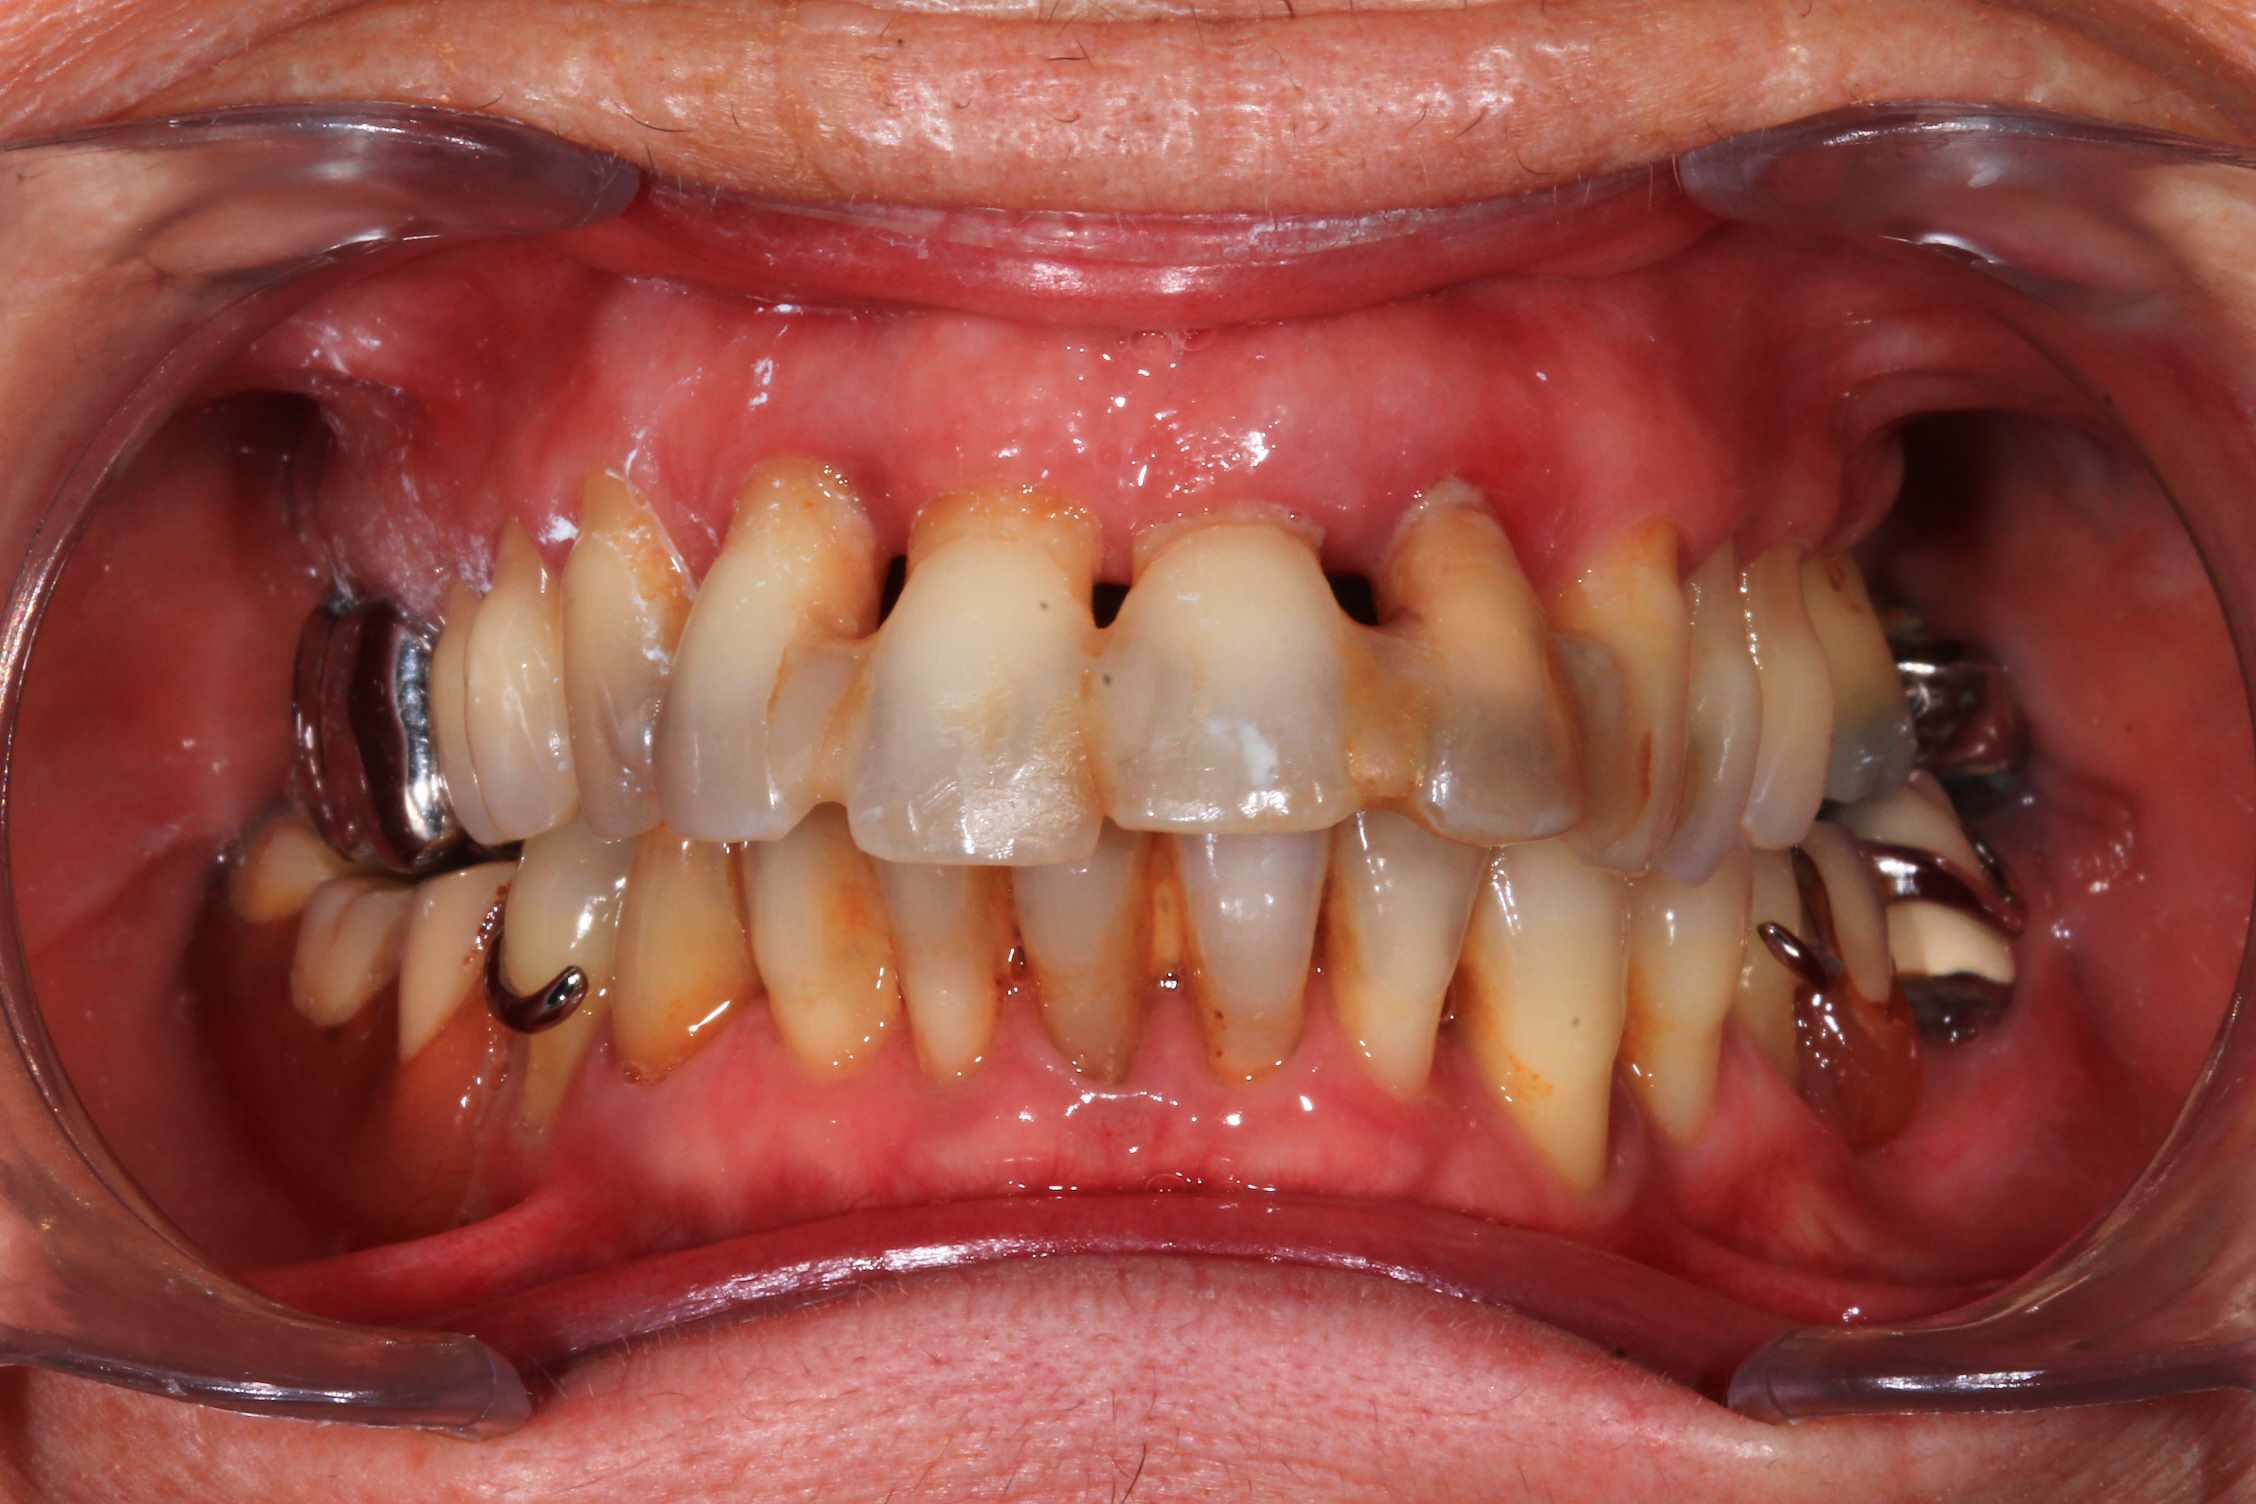

Cas 1 : patient ayant une 23 fracturée, avec 11 21 22 en mobilité terminale.

Planification des extractions, pose de 3 implants et mise en esthetique instantanée.

la seule chose qui m'interpelle, c'est de voir une bouche avec autant de travail (9 implants dont 6 anciens) et aussi peut de soins d'hygiène,...

:) . effectivement terrain paro chronique, déjà traité il y a quelques année a paris. Plus ou moins stabilisé, pas de saignement, un peu de tartre en bas. des mobilités importantes sur les incisives antérieures qui, avec la facture de la 23 ont emporté ma décision. Solution alternative : stellite ? dans un an, tu extrais les dents support de crohet. Bridge ? cela me semble plutôt casse gueule.

Donc, implant , sur un terrain qui n'est pas idéal, certes, mais c'est souvent le cas.